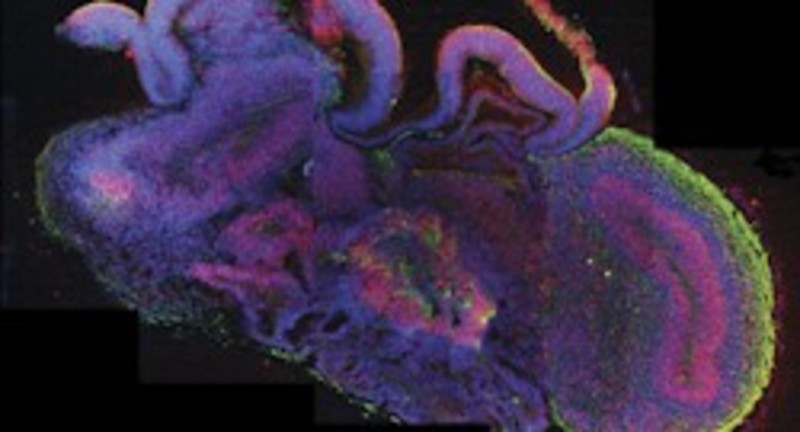

Los microcerebros que han desarrollado incluyen la corteza cerebral que cubre los dos hemisferios, compartiendo muchas semejanzas con la de un cerebro en sus etapas más tempranas de desarrollo.

Estos microcerebros, que incluyen la corteza cerebral que cubre los dos hemisferios, están formados por diferentes tejidos dispuestos en capas, cuya organización guarda muchas semejanzas con la de un cerebro en sus etapas más tempranas de desarrollo.